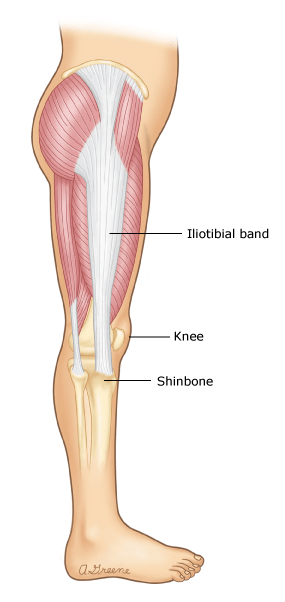

The iliotibial band (IT band) is a thick band of tissue that runs from your hip to the outside of your knee. ITBS occurs when this band becomes tight or inflamed, leading to pain and discomfort, particularly during activities that involve repetitive knee bending.

The hallmark symptom of ITBS is an aching, burning pain on the outside of the knee. The pain sometimes spreads up the thigh to the hip.